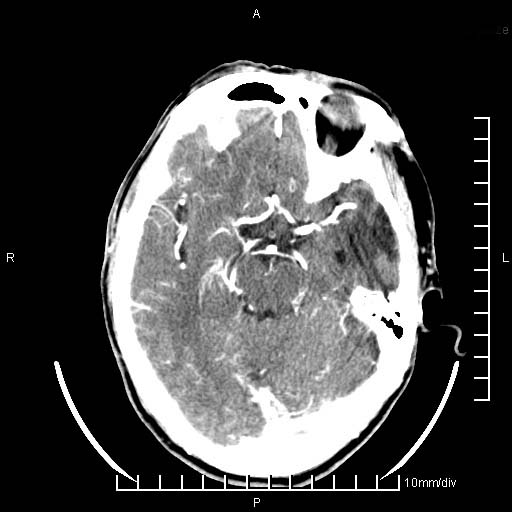

临床以双下肢浮肿,疼痛收治,无明显神经系统症状,既往无梗塞,出血病史。左颞叶见低密度灶,考虑什么?

考虑左侧颞叶脑软化灶。

无强化 无占位 软化灶吧

无强化、 无占位、局部脑沟增宽, 软化灶吧。